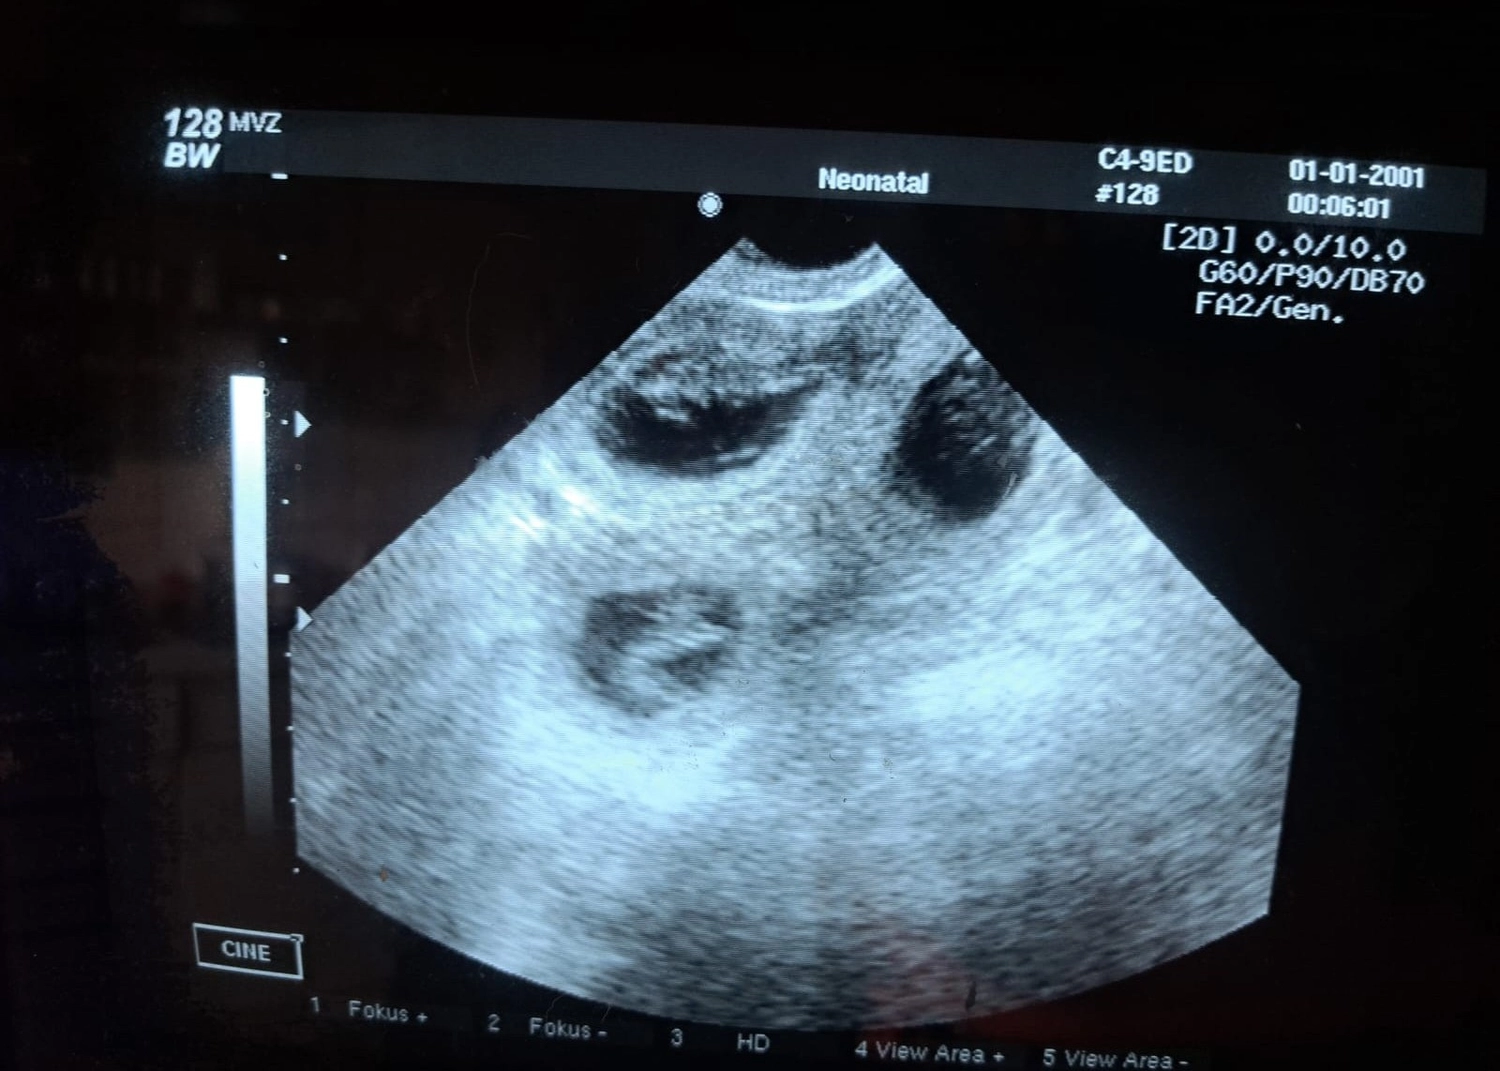

Die heutige Ultraschalluntersuchung bestätigte, dass Crazy trächtig ist.

Laut Tierarzt sind "mehrere Welpen" zu sehen!

Jetzt beginnt die spannende Wartezeit – wir hoffen, dass die Trächtigkeit weiterhin problemlos verläuft und dass alles gut geht. 🐾